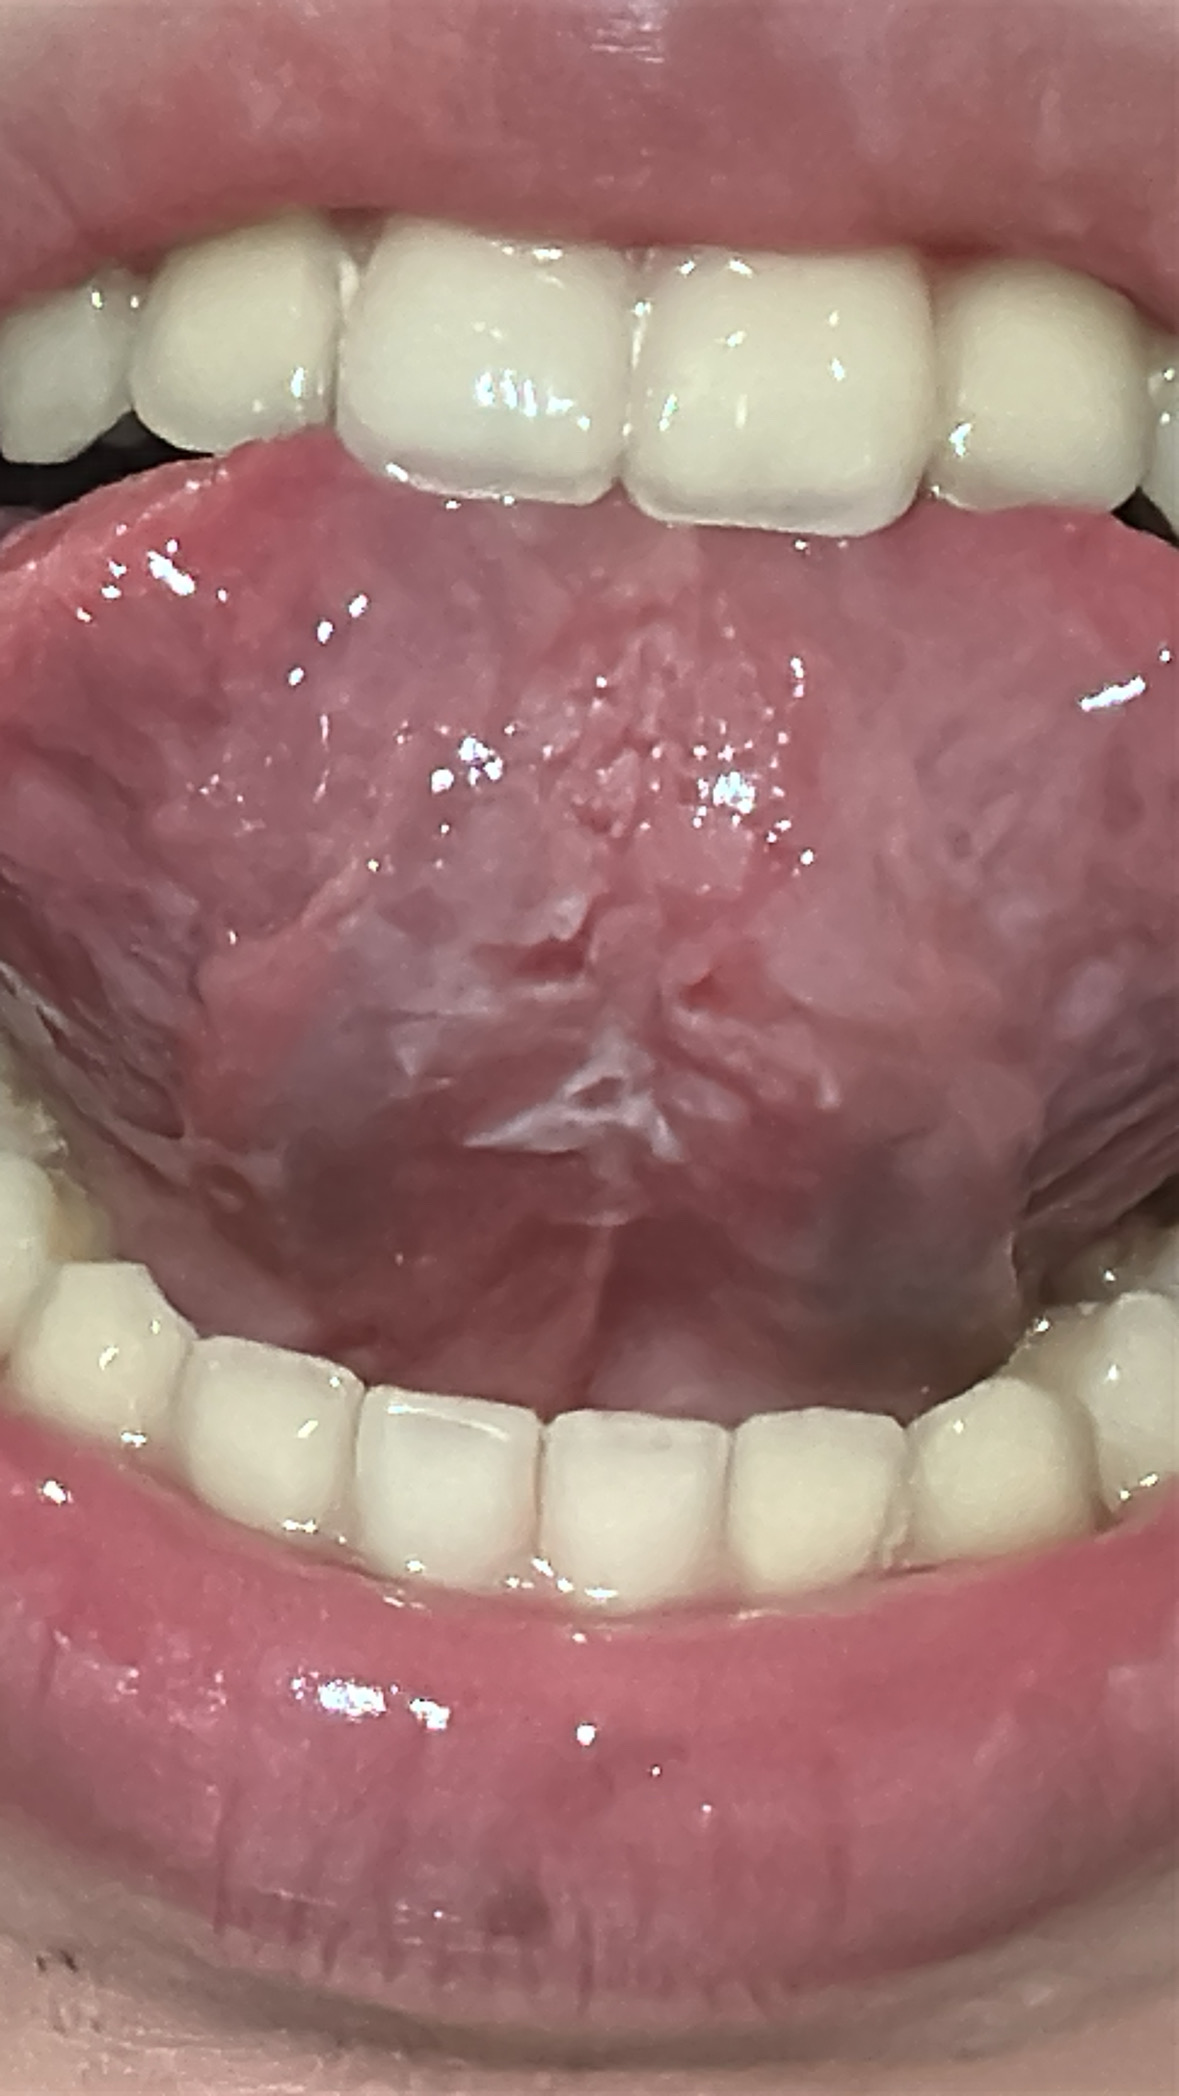

1 กันยายน 2568 21:46:48 #1 ใต้ลิ้นมีอาการลอก และเจ็บเวลายกขึ้น เป็นมาสามครั้งแล้วก็หาย แต่หายสองวันบ้าง 1 วันบ้าง https://haamor.com/media/create_topic/20250901214519.jpeg

| อายุ: 20 ปี เพศ: M น้ำหนัก: 49 กก. ส่วนสูง: 165ซม. ดัชนีมวลกาย : 18.00 (ค่ามาตรฐานคนเอเชีย=18.5-22.9) | |

3 กันยายน 2568 13:24:35 #2 แผลใต้ลิ้น เป็นๆหายๆ และมีอาการเจ็บเช่นนี้ ควรไปพบทันตแพทย์ หรือ ไปที่คณะทันตแพทยศาสตร์ เพื่อวินิจฉัยและรักษาให้หาย เนื่องจากผู้ถามไม่มีคำถามจึ